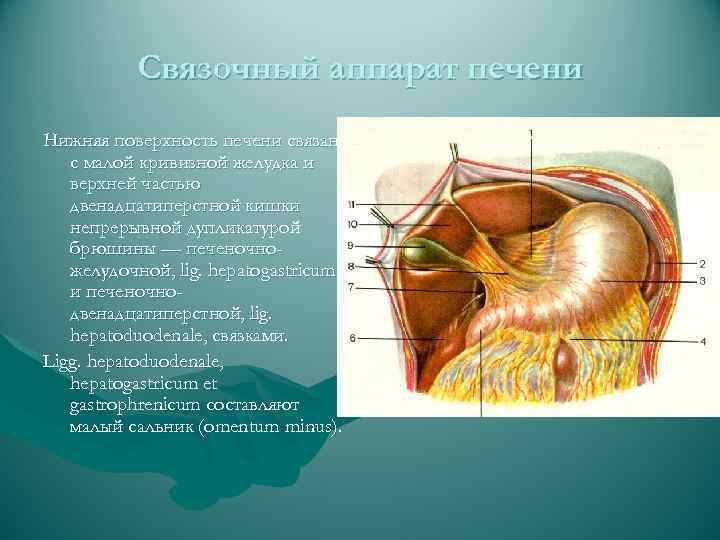

Связочный аппарат печени Нижняя поверхность печени связана с малой кривизной желудка и верхней частью двенадцатиперстной кишки непрерывной дупликатурой брюшины — печеночножелудочной, lig. hepatogastricum, и печеночнодвенадцатиперстной, lig. hepatoduodenale, связками. Ligg. hepatoduodenale, hepatogastricum et gastrophrenicum составляют малый сальник (omentum minus).

Связочный аппарат печени Нижняя поверхность печени связана с малой кривизной желудка и верхней частью двенадцатиперстной кишки непрерывной дупликатурой брюшины — печеночножелудочной, lig. hepatogastricum, и печеночнодвенадцатиперстной, lig. hepatoduodenale, связками. Ligg. hepatoduodenale, hepatogastricum et gastrophrenicum составляют малый сальник (omentum minus).